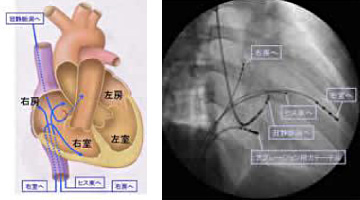

导管消融术

适应症:阵发性室上 性心动过速/房颤、室颤/房性期外收缩、室性期外收缩/各种心律失常